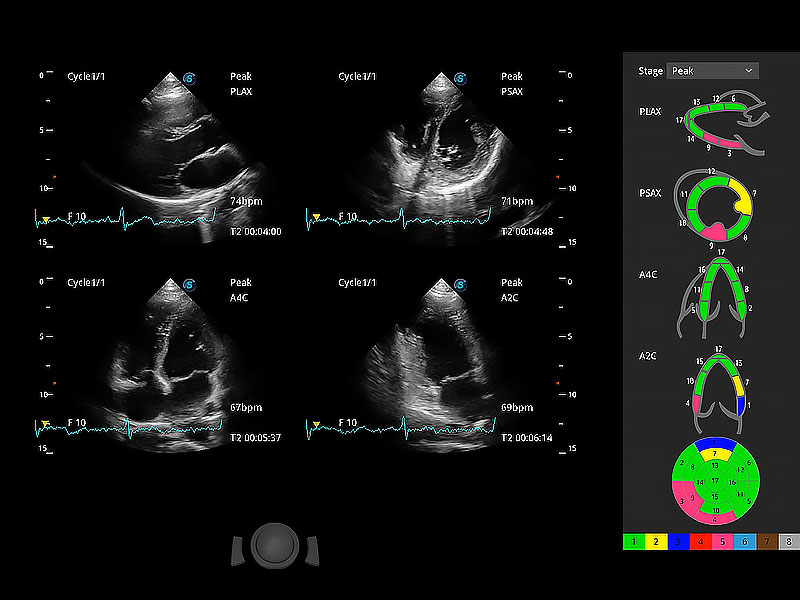

通過心肌識別技術(shù)與二維斑點追蹤技術(shù)相結(jié)合,對心臟的超聲圖像進(jìn)行量化分析。計算心肌17個節(jié)段的應(yīng)變、應(yīng)變率、速度、位移等,并通過牛眼圖的形式進(jìn)行呈現(xiàn)。

具備多種協(xié)議可選,同時支持17階段劃分法和專業(yè)的SE報告。